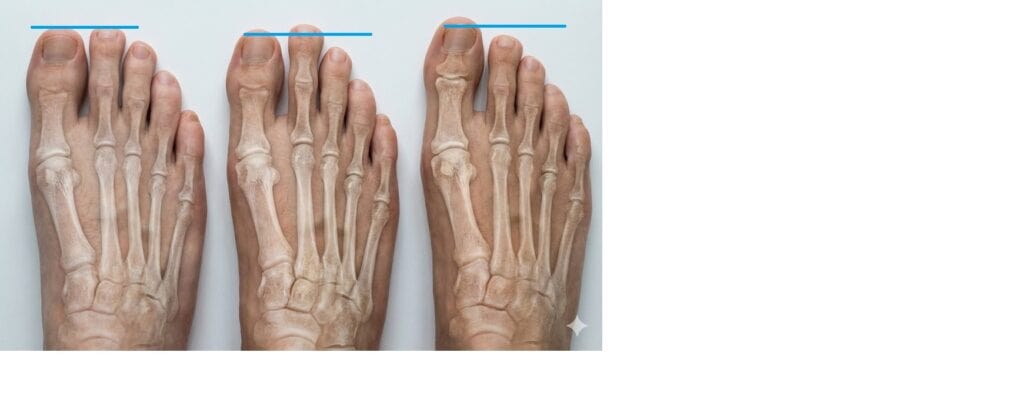

- Daylight Sign / V-Sign: נוצר רווח בין האצבע השנייה לשלישית (האצבעות נפרדות).

- Floating Toe: האצבע השנייה מתרוממת באוויר ולא נוגעת ברצפה בעמידה.

מיהו החשוד המיידי? אישה בגיל העמידה, עם הלוחית ולגוס, שאצבעה השנייה ארוכה מהראשונה.

הדגל האדום: אצבע שמתחילה "להיפרד" מחברותיה (V-Sign) או להתרומם באוויר.